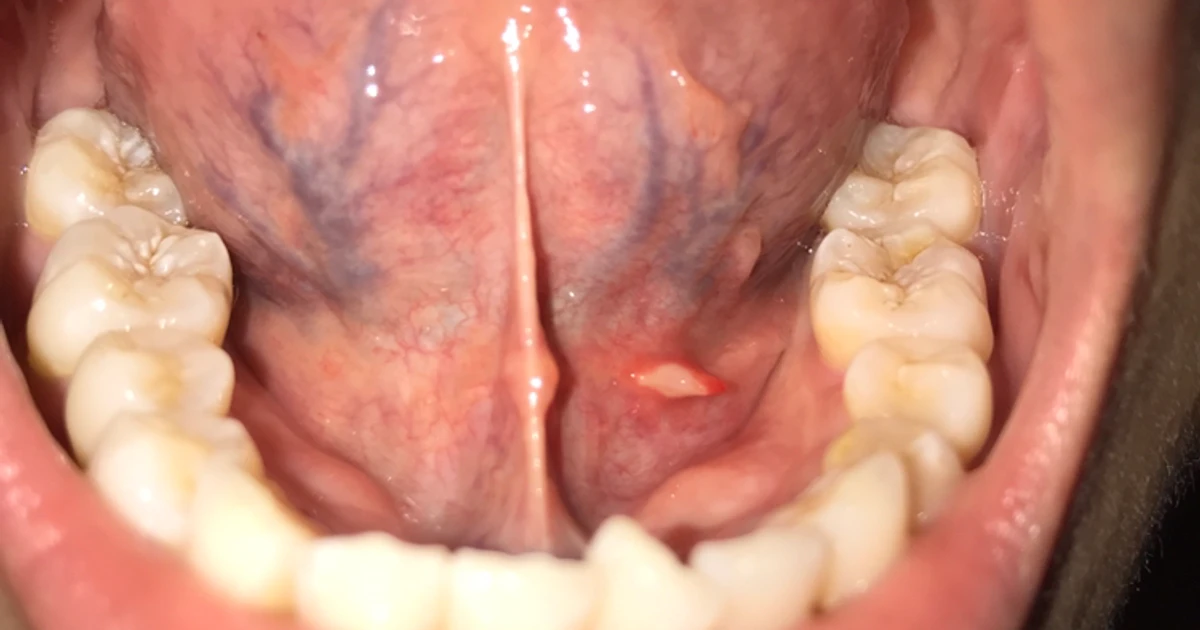

Do You have a Skin Tag Under Your Tongue, Plica Fimbriata? Tags Under Tongue They may be slightly raised or. Someone with hpv carries the virus in. bumps under the tongue can be harmless, or they can occur due to an underlying condition. human papillomavirus (hpv) can affect the inside of the mouth, the tongue, and the lips. how to identify tongue skin tags. understanding skin tags and their specific. Tags Under Tongue.

The doubletongue sign Cleveland Clinic Journal of Medicine Tags Under Tongue Skin tags are nothing more than small and fleshy benign growths. Read about 10 causes, symptoms, diagnosis, and treatment. They may be slightly raised or. how to identify tongue skin tags. common causes of tongue bumps include injuries, allergies, and infections. bumps under the tongue can be harmless, or they can occur due to an underlying condition.. Tags Under Tongue.